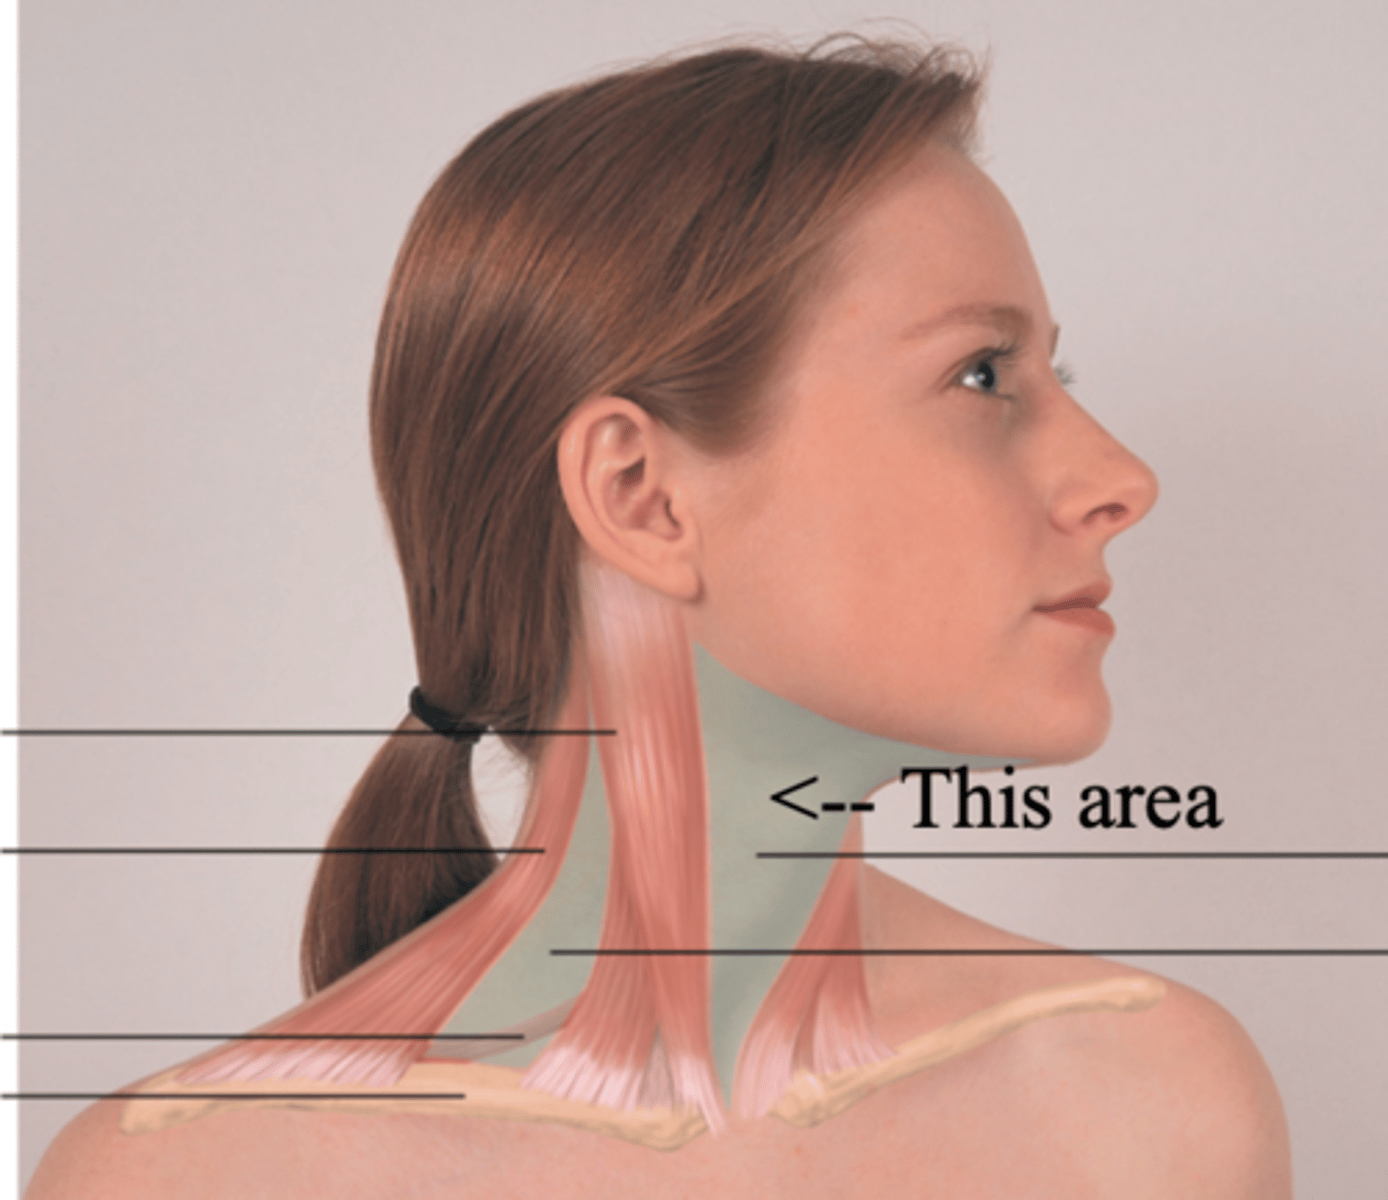

Anterior Triangle

The area that lies in front, between the sternomastoid and the midline of the body, with its base up along the lower border of the mandible and its apex down at the suprasternal notch

Posterior Triangle

The area of the neck between the sternocleidomastoid muscle and trapezius muscles